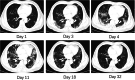

Case presentation: Laboratory findings showed high lactic acid level (2.1 mmol/L) and C-reactive protein (CRP, 48.8 mg/L), and low white blood cell count (1.96 × 109/L) in a 65-year-old Chinese man, who was diagnosed with severe COVID-19. CP was intravenously given twice, and hydroxychloroquine was orally administrated for a week (0.2 g, three times a day). The lactic acid and C-reactive protein levels remained high (2.1 mmol/L and 73.23 mg/L, respectively), while the arterial oxyhemoglobin saturation decreased to 86% with a low oxygenation index (OI, 76 mmHg) on day 4 after CP transfusion. His temperature returned to normal and the OI ascended above 300 on day 11. Moreover, the RNA test remained positive in throat swab, and computed tomography revealed severe pulmonary lesions on day 11 after admission.